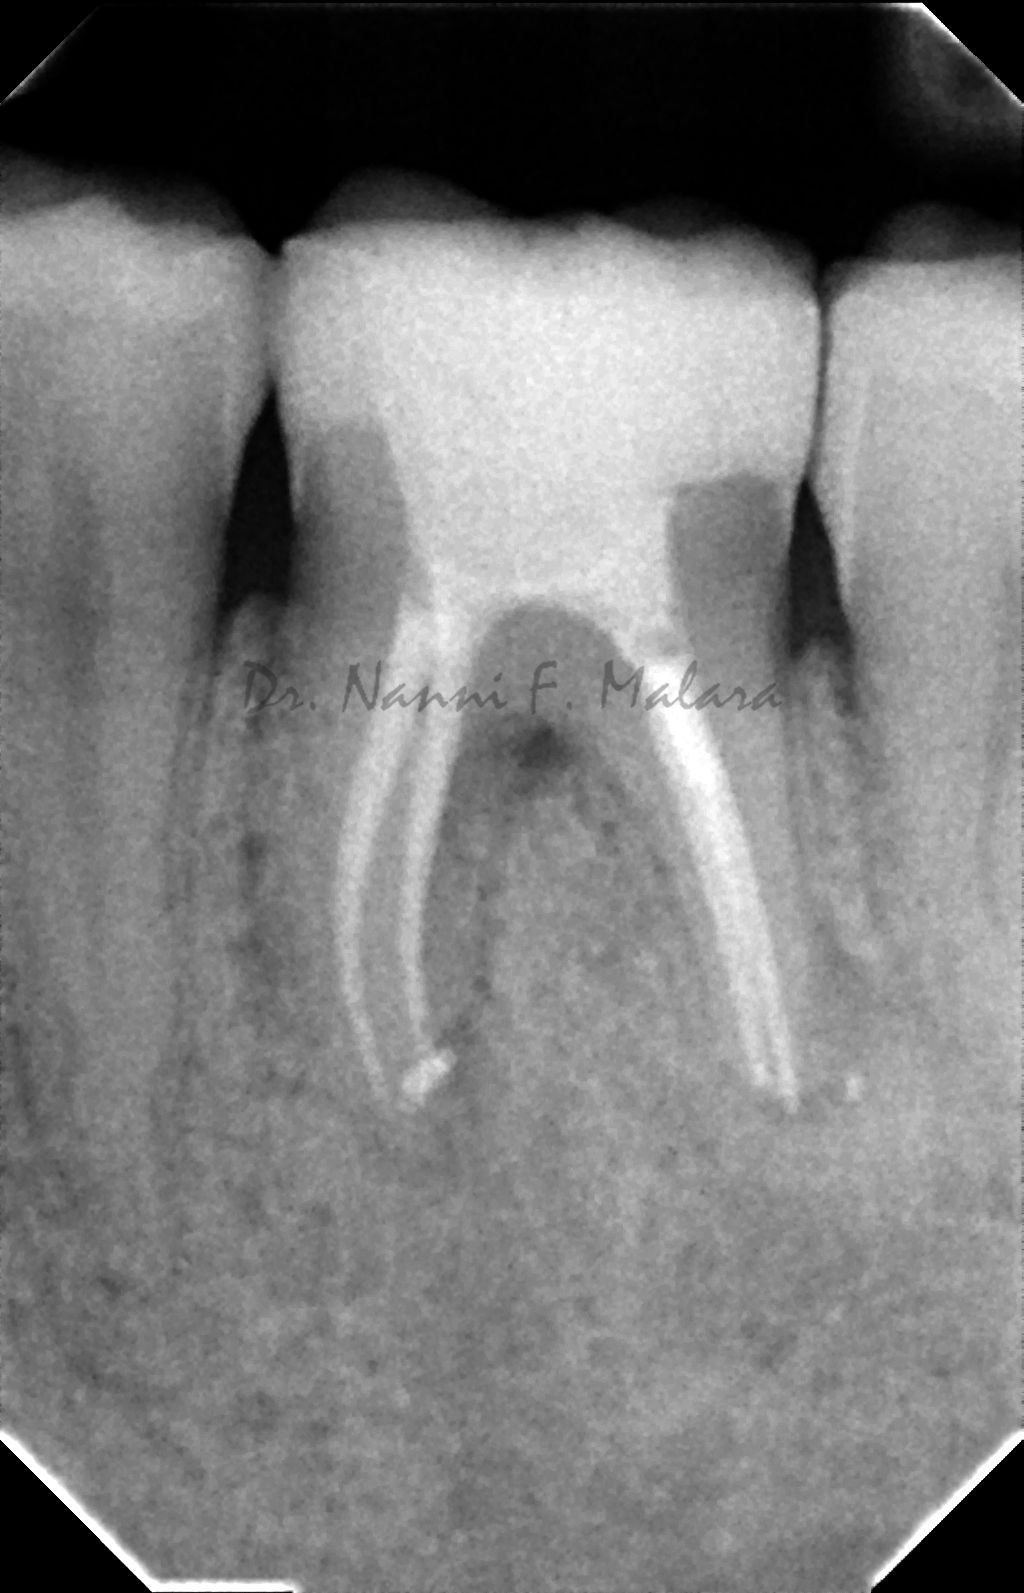

Molare affetto da lesione periapicale a carico di entrambe le radici (Alla radiografia si presentano come aree scure intorno alle radici)

Terapia endodontica con sigillo tridimensionale dei canali radicolari

Controllo della guarigione a 7 mesi dalla terapia endodontica (Alla radiografia si nota come le lesioni ossee siano guarite, e la densità della trabecolatura ossea sia tornata alla normalità)